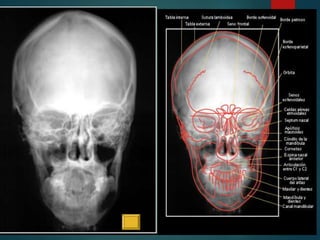

Este documento proporciona instrucciones para realizar diferentes proyecciones radiográficas del cráneo, incluyendo las proyecciones anteroposterior (AP), submentovertex (SMV), parietoorbitaria y transorbitaria de Guillen. Describe los ángulos y posiciones requeridos para cada proyección y las estructuras óseas que deberían ser visibles en cada imagen resultante.